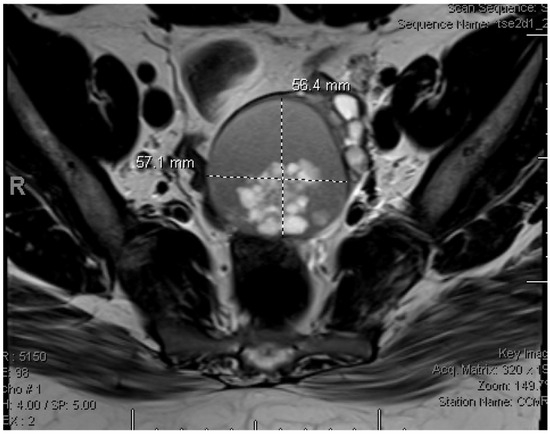

2. Detailed Case Description